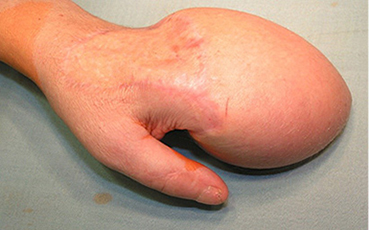

Vaizdas po I rekonstrukcijos etapo. Prigijęs kirkšnies lopas vėliau atskirtas nuo donorinės vietos ir perskeltas tarp III ir IV pirštų, suformuojant dviejų pirštų kompleksus. Stebimas minkštųjų audinių perteklius, ypač ties IV pirštu, kur buvusi lopo „kojytė“ ir darbiniame suformuoto piršto paviršiuje atsivėrusi opelė (5–8 pav.)

Pacientė operuota ranka naudodavosi buityje, tačiau ilgiau padirbus išopėdavo darbiniai pirštų paviršiai (8 pav.), todėl nuspręsta iš dešinės pėdos persodinti laisvąjį įnervuotą fasciokutaninį I tarpupirščio nugarinės pėdos arterijos lopą. Pacientė hospitalizuota ir 2006 m. birželio mėn. operuota. Atliktas zigzaginis pjūvis delne, išpreparuotos arterijos ir nervų bigės, rieše – galvinė vena. Pašalintas audinių perteklius III ir IV pirštų delniniuose paviršiuose, desindaktilizuota V piršto bigė. Nuo pėdos kartu su nugarine pėdos arterija ir poodine vena atpreparuotas fasciokutaninis I tarpupirščio pėdos nugarinio paviršiaus lopas, įnervuotas giliuoju šeiviniu nervu ir blauzdos odos nervu. Lopas perkeltas ant rankos, donorinė sritis pėdoje padengta perforuota skelta oda iš dešinės kirkšnies. Lopas plaštakoje prisiūtas į defekto vietą. Naudojant operacinį mikroskopą, susiūtos venos, lopo kraujagyslė susiūta su paviršinio lanko arterija, gilusis šeivinis nervas susiūtas su smiliaus savuoju nervu, blauzdos odos nervas susiūtas su III–IV pirštų bendruoju nervu. Plaštaka imobilizuota gipso longete.